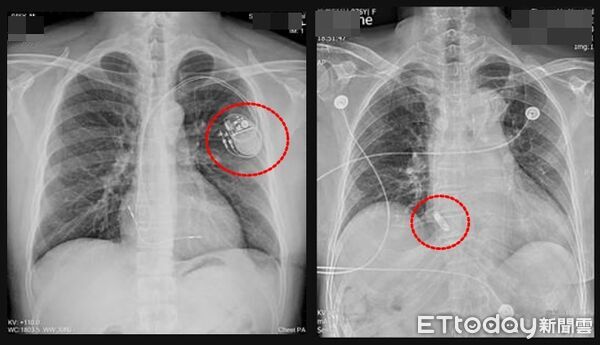

▲圖左為傳統心臟節律器,圖右為無導線心臟節律器,體積小如膠囊,可直接植入心腔 。(圖/雙和醫院提供)

林中行指出,考量患者平日熱愛運動,經醫療團隊評估,決定採心導管微創方式植入右心房無導線心臟節律器,裝置體積如膠囊,可直接置放於右心房或右心室內,無需導線及胸前囊袋,可降低感染及氣胸等併發症,外觀也不易察覺,手術約1小時完成,術後3天即出院,回診狀況良好。